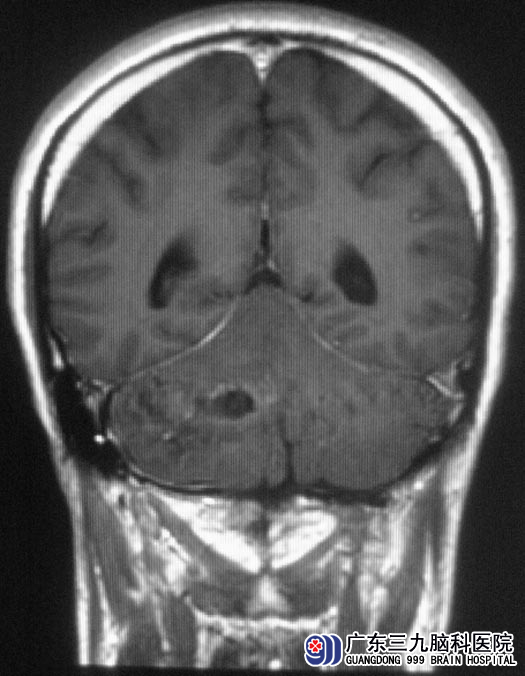

梁先生一周前出现头晕,可自行缓解。症状反复出现,并伴有头痛、走路不稳,为求放心去医院检查。头颅CT提示:右侧小脑占位性病变,广东三九脑科医院MR提示肿瘤大小约5.94cm×3.81cm×3.69cm,初步考虑为血管母细胞瘤。

综合神经外科鲁明主任主刀,在全麻下行后正中入路右侧小脑半球血管母细胞瘤切除术,术中见肿瘤呈囊实性,囊液呈草绿色,沿外侧切除实性部分,肿瘤呈粉红色血管团,质软,血供丰富,在显微镜下予肿瘤切除,手术顺利。术后,梁先生走路较术前好转,康复出院。术后病理结果为:血管母细胞瘤。